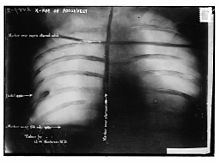

Assassination attempt

While Roosevelt was campaigning in Milwaukee, Wisconsin, on October 14, 1912, a saloonkeeper named John Schrank shot him, but the bullet lodged in his chest only after penetrating his steel eyeglass case and passing through a thick (50 pages) single-folded copy of the speech he was carrying in his jacket. Roosevelt, as an experienced hunter and anatomist, correctly concluded that since he was not coughing blood, the bullet had not completely penetrated the chest wall to his lung, and so declined suggestions he go to the hospital immediately. Instead, he delivered his scheduled speech with blood seeping into his shirt. He spoke for 90 minutes. His opening comments to the gathered crowd were, "Ladies and gentlemen, I don't know whether you fully understand that I have just been shot; but it takes more than that to kill a Bull Moose." Afterwards, probes and x-ray showed that the bullet had traversed three inches (76 mm) of tissue and lodged in Roosevelt's chest muscle but did not penetrate the pleura, and it would be more dangerous to attempt to remove the bullet than to leave it in place. Roosevelt carried it with him for the rest of his life.

Because of the bullet wound, Roosevelt was taken off the campaign trail in the final weeks of the race (which ended election day, November 5). Though the other two campaigners stopped their own campaigns in the week Roosevelt was in the hospital, they resumed it once he was released. The bullet lodged in his chest caused his chronic rheumatoid arthritis – which he had suffered from for years – to get worse and it soon prevented him from doing his daily stint of exercises; Roosevelt would soon become obese as well. Roosevelt, for many reasons, failed to move enough Republicans in his direction. He did win 4.1 million votes (27%), compared to Taft's 3.5 million (23%). However, Wilson's 6.3 million votes (42%) were enough to garner 435 electoral votes. Roosevelt had 88 electoral votes to Taft's 8 electoral votes. This meant that Taft became the only incumbent president to place third in a re-election bid. But Pennsylvania was Roosevelt's only eastern state; in the Midwest, he carried Michigan, Minnesota and South Dakota; in the West, California and Washington; he did not win any southern states.